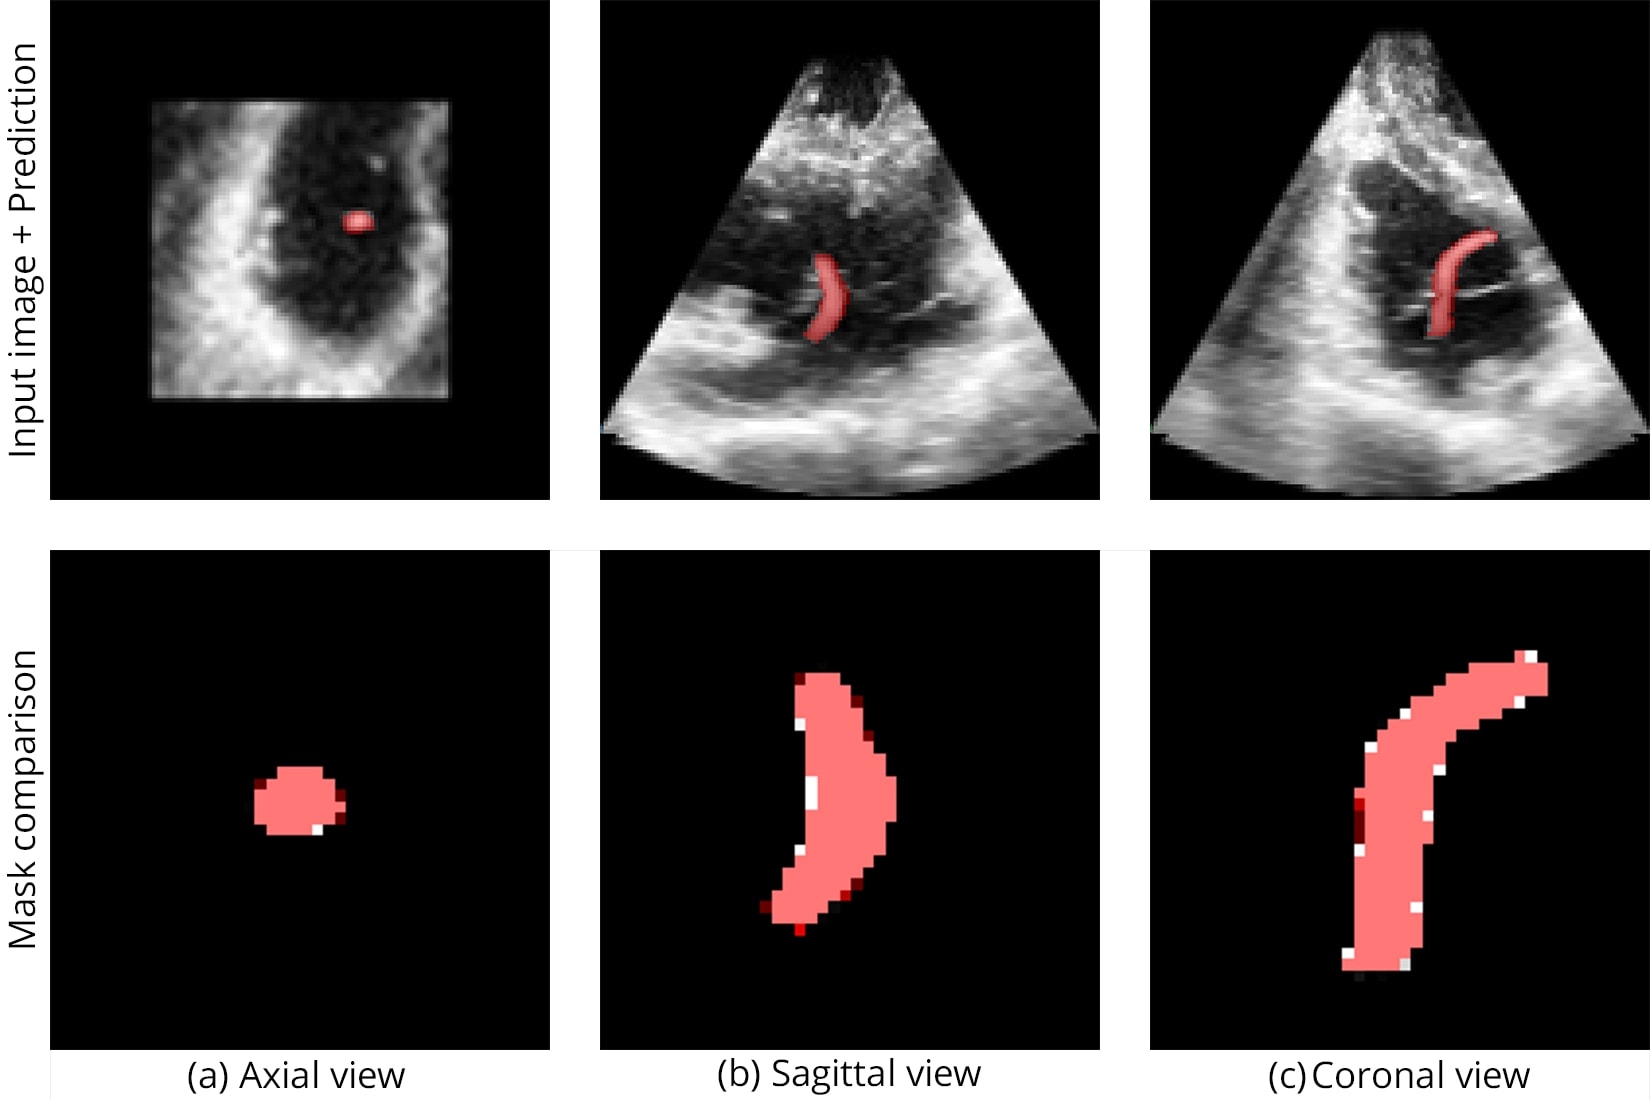

The catheter used in this study is shown in Figure 1, while Figure 2 illustrates the challenging visibility of catheters in raw ultrasound data.

The V-net architecture achieved high spatial precision in localizing catheters despite strong speckle noise and anatomical occlusion:

Segmentation accuracy on synthetic and real samples is shown in Figure 5 and Figure 6, and the comparison with other networks is presented in Figure 7.